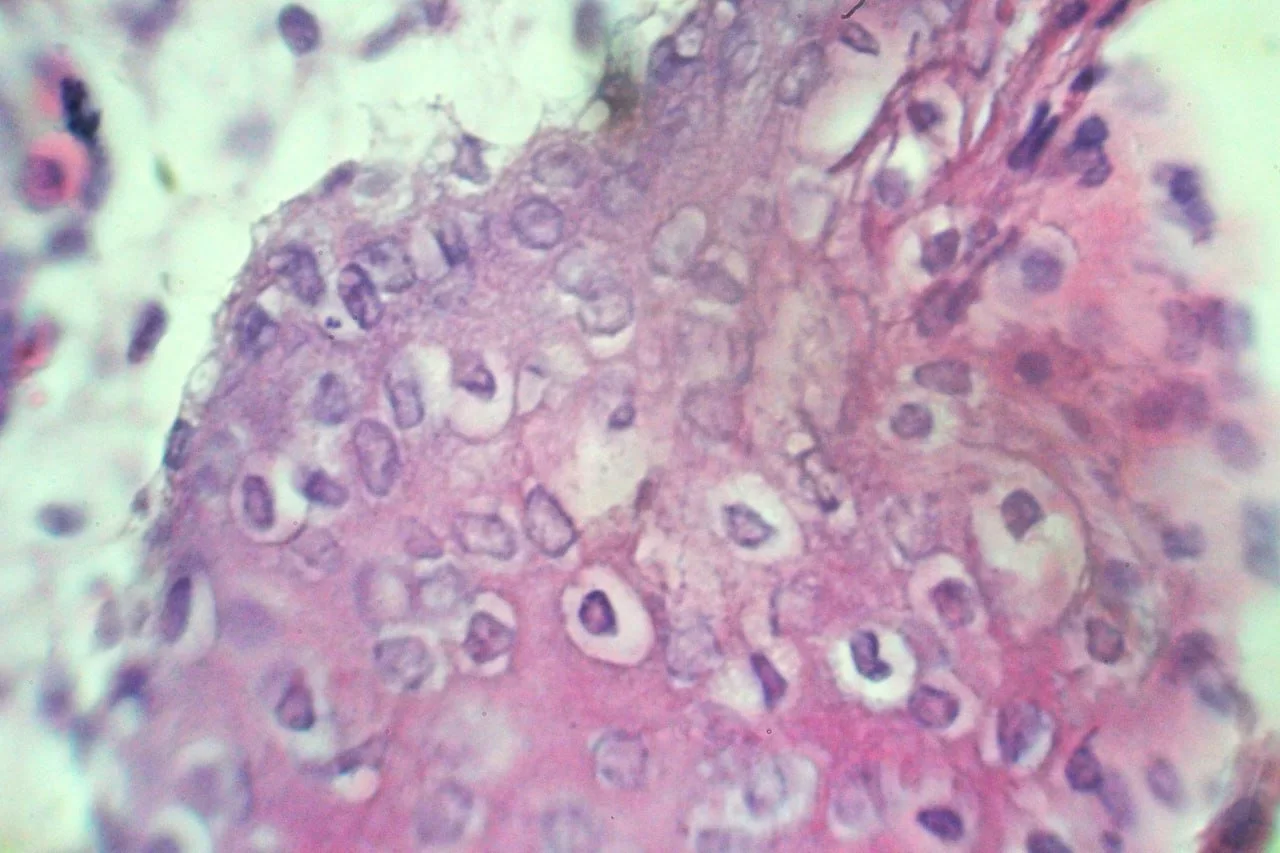

ضمن الخطة البحثية لقسم امراض الدواجن والاسماك تم عزل فيروس جدري الدجاج وفيروس جدري الحمام من الحالات الواردة للقسم